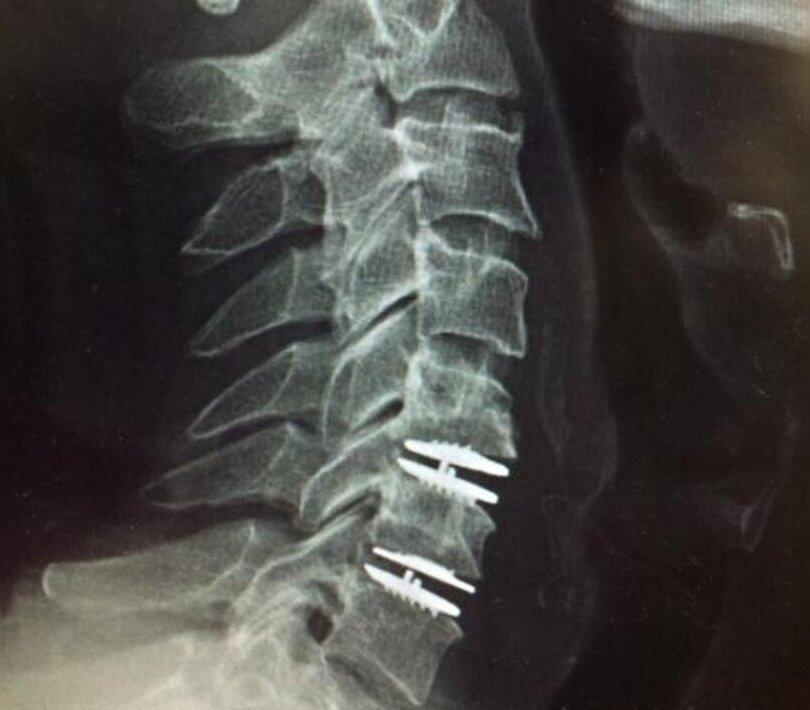

Disc replacement surgery is an advanced procedure designed to address pain caused by damaged or degenerated spinal discs. By replacing the affected disc with an artificial one, this surgery restores normal spine function and mobility.

This procedure is particularly beneficial for those with chronic back pain due to herniated or degenerative discs. Compared to traditional spinal fusion, disc replacement surgery allows for a more natural range of motion, offering significant relief and preventing the degeneration of nearby discs.